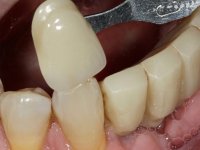

Após estudo imagiológico foi planificada a colocação de dois implantes de 3.3 mm de diâmetro e 10 mm de comprimento. No dia da cirurgia foram extraídos os dentes 42 e 32 e removido o implante. Os implantes foram colocados na zona dos alvéolos tendo o cuidado de lingualizar um pouco o seu posicionamento. Foi feita uma impressão pela técnica de moldeira aberta com o retalho aberto para a confeção da ponte provisória imediata. Enquanto a impressão foi para o laboratório, foram colocados parafusos de cicatrização altos e feita a sutura da ferida cirúrgica. A paciente esperou 2 horas na sala de espera enquanto no laboratório era confecionada a ponte provisória. A ponte provisória imediata aparafusada foi colocada e o seu assentamento controlado imagiologicmente. Passados 3 meses foi realizada a impressão definitiva com uma técnica de moldeira aberta. Nessa consulta aproveitamos para polir a ponte provisória com taças de borracha para que os tecidos moles pudessem maturar em melhores condições. Foi feita a recolha de informação para caracterizar da melhor forma a estrutura monolítica em Zr. Foram utilizadas guias de cor para a cerâmica de tonalidade coronária e gengival. No laboratório foi confecionada uma ponte em Zr. aparafusada que foi cuidadosamente caracterizada. Após aprovação pela paciente foi colocada definitivamente em boca. O aperto foi feito com uma chave dinâmica com 35 N de torque. Os orifícios foram tapados com teflon e obturados com resina composta.